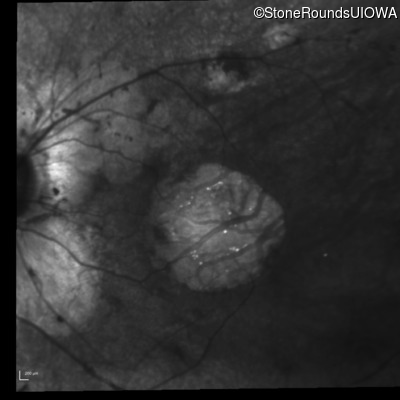

Infrared Fundus Photograph - Right - 20/125

Exemplar